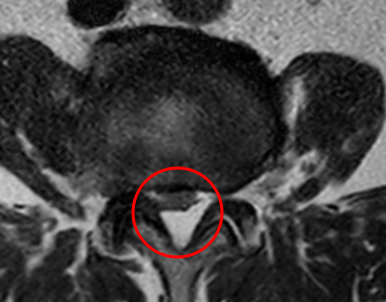

治療前

┃検査・診断

腰椎MRIを確認したところ、赤い枠内のL3/4で脊柱管が狭窄しているのを確認しました。そのため痛みの原因はL3/4部分の「脊柱管狭窄症」だと診断しました。